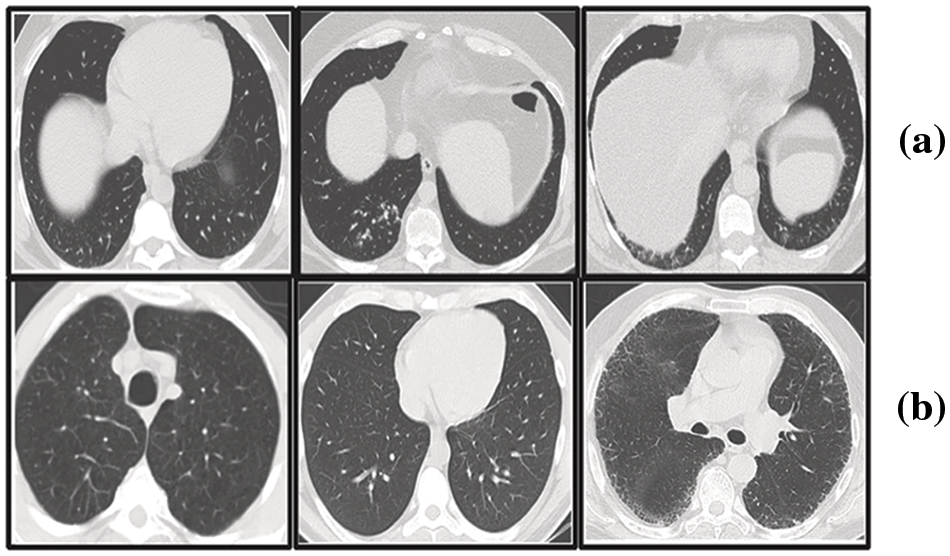

In our research, we have utilized the SARS-CoV-2 CT scan dataset compiled by Soares et al. [28], which encompasses a total of 2481 2D CT images. This dataset is bifurcated into two subsets: one containing 1252 CT scans from patients diagnosed with COVID-19, and the other comprising 1229 CT scans from individuals not infected by the virus. We sourced our data from a cohort of 120 patients based in Sao Paulo, Brazil, with the COVID-19 positive group including 32 males and 28 females, and the uninfected group consisting of an equal number of males and females, 30 each. Access to the dataset is available at www.kaggle.com/plameneduardo/sarscov2-ctscan-dataset. The two classes of the dataset can be shown in Fig. 6.

Figure 6: Representative sections from the SARS-COV-2 2D-CT-scan collection featuring both COVID-positive and COVID-negative cases